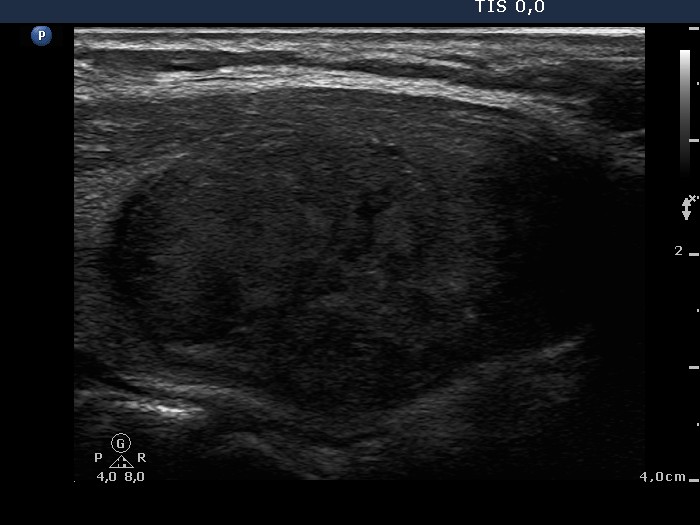

Ultrasonography: the thyroids were echonormal. There was an echonormal nodule occupying almost the entire right lobe. The lesion displayed a halo sign, cystic degeneration and presented perinodular blood flow.

5 sessions of sclerotherapy were performed. We demonstrate the 1st and 4th session.